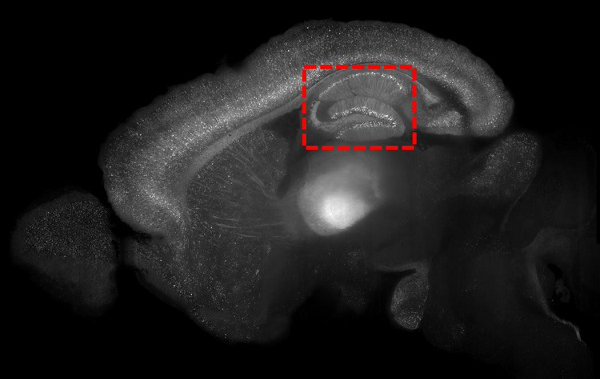

Black and white brain scan with a section outlined in a rectangle.

Cross section of a mouse brain showing a ‘snap shot’ of how memory is represented across the whole brain. Each of the shining cells are neurons that were activated when the mouse was developing the infantile memory. The structure in the red box is the hippocampus.